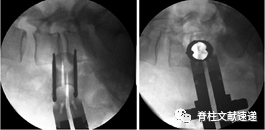

(9)椎间盘切除术和终板准备的并发症

在切除椎间盘对侧过程中,建议反复进行影像学透视,并应谨慎进行。建议在此步骤中使用钝性手术工具,以避免对侧腰肌和腰丛损伤。另一个技术建议是能够应用椎间盘切除术中的角度调整操作,终板的准备和cage放置:首先将管状牵开器倾斜放置,然后在准备终板的过程中,对器械进行90度的角度校正。

Chang等人发表了一个在OLIF手术中出现腹侧硬脑膜囊撕裂的病例。这一并发症是由于在准备终板的过程中,部分外科医生在透视下迷失方向,以及失败的角度调整操作。

图示:术中技术演示正确准备终板,避免过度准备。(A) 正位透视显示造影剂和终板之间没有间隙;(B)侧位透视显示将cage插入的位置。